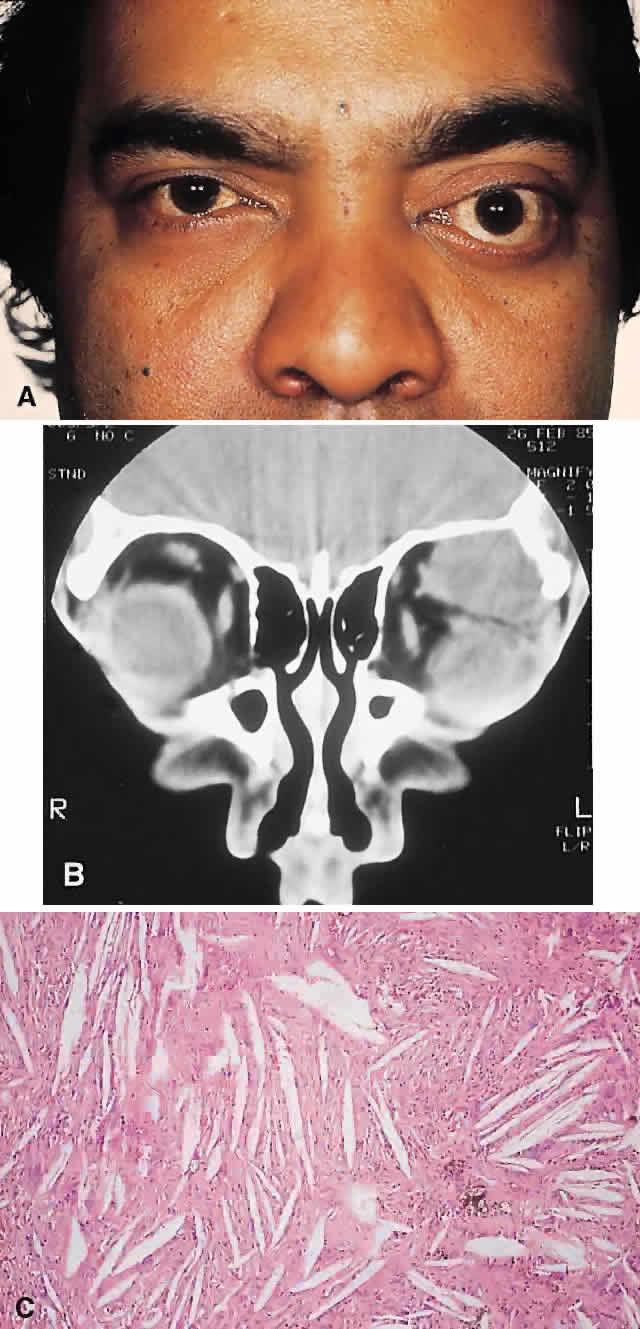

| The above clinical patterns correlate reasonably well with the following